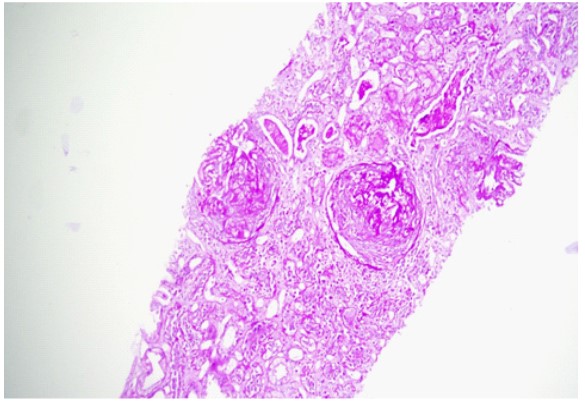

The patient was a 32 years old doctor; he was previously healthy till September 2023. He had sneezing, impaired hearing and epistaxis for 1 week duration; and, he was treated as a case of acute suppurative otitis media. He was given co-amoxiclav 625 mg 3 times a day for 10 days and topical nasal steroid spray. It was followed by episcleritis of left eye, myalgia and polyarthritis involving large joints: both knee joints, elbow joints, wrist joints and shoulder joints. They were swollen; very tender; non-migratory in nature; and, disturbing sleep even with diclofenac 50 mg 3 times a day. Initial clinical impression was acute polyarthritis due to virus (Chikungunya virus infection) or bacterial (acute rheumatic fever) in etiology. Blood for complete picture showed normal total WBC count, hemoglobin and platelet count. Inflammatory markers were raised; ESR was 10 mm in 1st hour; CRP was 6.7 mg/L; ASO titer was 200 units; serum creatinine was normal (0.93 mg/dl); uric acid was 7.4 mg/ dl. Anti-CCP was negative and RA test was positive. As RA test was positive; the likelihood of seropositive rheumatoid arthritis (RA) was also considered though several points were against it. Negative points against RA were male sex, relatively short duration of joint symptoms (less than 2 weeks), involvement of large joints. Rheumatologist suggested to start steroids, methotrexate, calcium supplements for possible seropositive rheumatoid arthritis and allopurinol for hyperuricemia. One month later, erythematous tender maculo-papular rash appeared on both shin, foot, chest and bilateral poly-chondritis developed. It is shown in photo [1-6]. Episcleritis improved though myalgia and polyarthritis were worsening. Then, he had puffy face; serum creatinine suddenly rose to 7.2 mg/dl. Blood ANA was negative. Features were highly suggestive of acute kidney injury due to acute interstitial nephritis or analgesic nephropathy. His urine output was normal. Meanwhile, he was having low grade fever. Full blood count showed normal; total WBC count was upper normal limit (12.0x109/L); hemoglobin was 12.9 gm/dl; platelet count was 406x109/L. Inflammatory markers were rising rapidly; ESR became high (70 mm in 1st hour); CRP rose to 89 mg/L. Uric acid remained high 8.2 mg/dl; liver function tests were normal; and random blood sugar was 103 mg/dl. Blood urea was very high 142 mg/dl; and, serum creatinine was very high too (8.2 mg/dl); serum potassium was 5.58 meq/L. Chest radiograph was normal. It is revealed in photo [7]. Ultrasound kidney was suggestive of bilateral mild nephropathy. In ANCA testing, p-ANCA was negative and c-ANCA was positive. Both antiproteinase 3 antibody and anti-myeloperoxidase antibody were negative. Renal biopsy was done. The features were suggestive of a pauci- immune crescentic glomerulonephritis; all glomeruli showed circumferential cellular crescents; the underlying glomerular tufts showed no increase cellularity; no basement membrane thickening; no segmental lesion; tubular injury with flattening; denudation of lining epithelium of tubules; some tubules had PAS positive hyaline casts within; no significant tubular atrophy; the interstitium appeared oedematous with no fibrosis or significant inflammation; no evidence of vasculitis. In immunofluorescence staining, all were negative: no immune deposits; IgG negative; IgM negative; IgA negative; C3 negative; C1q negative; Kappa negative; and Lambda negative. There was ‘7/7 ‘cellular crescents with underlying tufts showing no increase in cellularity. It is illustrated in photo [8,9]. He was given aggressive treatment to save kidney with rituximab, methylprednisolone and cyclophosphamide. Nonetheless, his urine output was falling; serum creatinine was rising; and, features of fluid overload set in. Therefore, rescue hemodialysis was initiated after fourth dose of rituximab. However, the patient suffered dyspnoea at rest at the day after last (third) dose of intravenous cyclophosphamide. He continued to have orthopnea, falling SaO2 even after removal of fluids with hemodialysis. Therefore, high flow oxygen was initiated. He was treated as a case of ARDS with Continuous Positive Airway Pressure (CPAP); and, he recovered over one month. Ultrasonogram done 2 months later revealed bilateral nephropathy; the size of right kidney was 10.6 cm; left kidney was 11 cm; cortical echo was increased; cortico-medullary junction was blurred; no stones nor hydronephrosis; and trace amount of ascites was seen in pelvic cavity. Therefore, he continued maintenance hemodialysis; and, he was waiting for living donor kidney transplant. As he required 5 anti-hypertensive drugs to keep blood pressure at 150/90 mmHg, renal doppler was done to exclude renal artery stenosis; it was normal. And renal angiogram did not reveal stenosis or aneurysm. His medications were Atorvastatin, Ranitidine, Carvedilol 25 mg BD, Nifedipine Retard 40 mg TDS, Aldactone 25 mg OD, Telmisartan 80 mg HS, Hydralazine 25 mg QID, Duracard 8 mg BD, Callog 1 OD, Medixon 4 mg OD, S/C Erythropoietin 4000IU 3 times/ week, Selvelamer 400 mg TDS, Ferrium XT 1 OD. He has been on maintainance hemodialysis 3 times per week till now.

Figures 8: Histology showing crescentic glomerulonephritis.

Figures 9: Histology close-up view showing crescents.